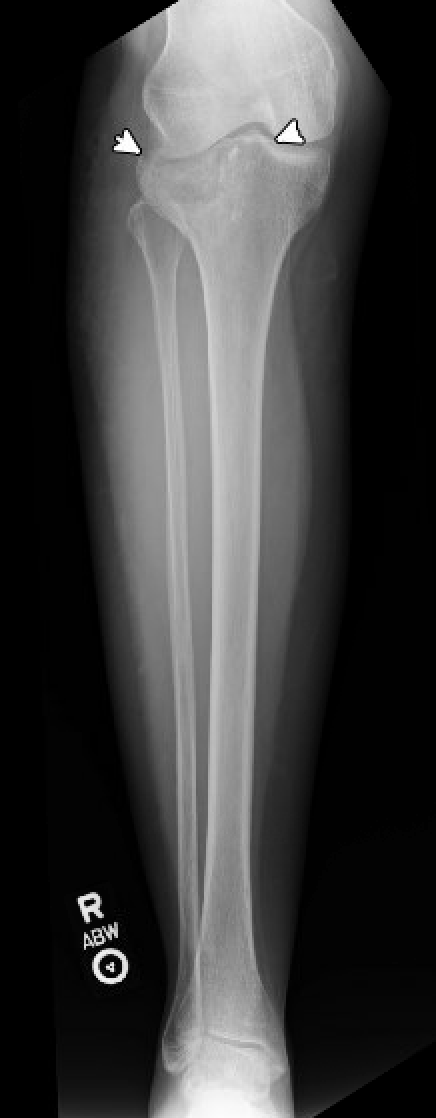

This film comes from a 47 year old woman who missed a step coming off of the bus and presented to the emergency room with right knee pain with a significant effusion. There is a depression of the lateral tibial plateau as indicated by the arrows.